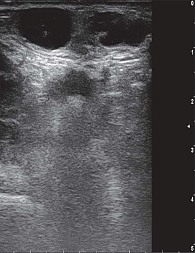

Рис. 1. Эхограмма правостороннего мастита у 12-летней девочки

Мастит – воспаление паренхимы и стромы МЖ, клинически проявляющееся локальной болезненностью и уплотнением, гиперемией кожи, лихорадкой и/или выделениями из соска [1, 9]. Существуют неонатальные, лактационные и нелактационные формы [1, 9]. В неонатальном периоде (до пяти недель жизни) мастит встречается у представителей обоего пола, нередко на фоне влияния материнских гормонов и вторичного инфицирования [1, 9]. Лактационный мастит связан с проникновением бактерий (чаще стафилококков и стрептококков) через трещины соска [1, 9]. В подростковом возрасте нелактационный мастит ассоциируют с инфекцией при эктазии протоков или метаплазии протокового эпителия [1, 9].

При УЗИ кожа и подкожно-жировая клетчатка утолщены, граница между слоями нечеткая, определяется гипоэхогенная зона отека, при цветовом дуплексном картировании кровоток усилен [5–7, 10]. У девочек при мастите часто лоцируются сложные кисты МЖ с гиперэхогенными перегородками, гипо- и анэхогенными участками внутри [5, 10]. При формировании абсцесса может визуализироваться гиперэхогенная капсула, внутри которой участок с гетерогенной структурой определяется только по периферии образования [5, 7, 10].

Эхографические признаки: утолщение кожи и гиподермы, размытость границы слоев, гипоэхогенный отек. При выполнении цветового допплеровского картирования (ЦДК) отмечается усиление кровотока [5–7, 10]. Иногда встречаются сложные кисты с перегородками и смешанной эхогенностью [5, 10]. Абсцесс визуализируется как образование с плотной гиперэхогенной капсулой и гетерогенным содержимым, васкуляризация – преимущественно по периферии (рис. 1) [5, 7, 10].